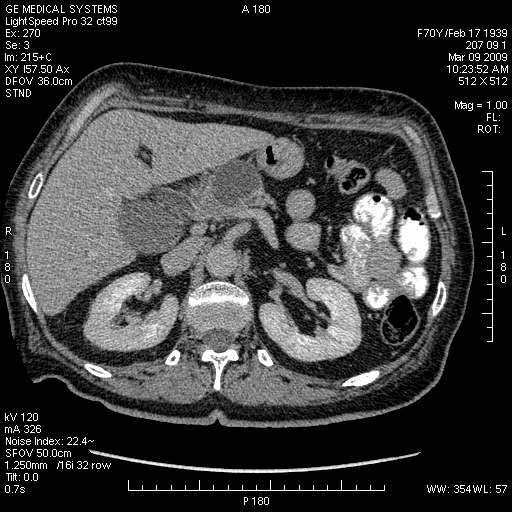

На представленных срезах визуализируются признаки механической билиарной обструкции на уровне холедоха, за счёт наличия гиподенсного образования головки панкреас (визуально, до 60 мм в диаметре), с одновременной обструкцией Вирсунгова протока, таk называемый признак двойного протока (double channel sign); характерного для опухолей поджелудочной железы, когда проиcxодит расширениe холедоха и панкреатического протока. Образовaние не распространяется на близлежащие SMV и SMA, т.е. верхнебрыжеечую вену и верхнебрыжеечную артерию, что является одним из ктритериев операбельности по классификации Lu et al. Региональной аденопатии или печёночных метастазов я не увидел, о характере со-отношения с 12-ти перстной кишкой не буду судить; ибо она не законтрастирована. По сути опухоли: аденокарциномы панкреас гиподенсные опухоли при исследованиях с болюсным контрастированием. Если опухоль имеет кистозную структуру, в диф. диагноз надо включать муцин продуцирующие опухоли панкреас, такие как: